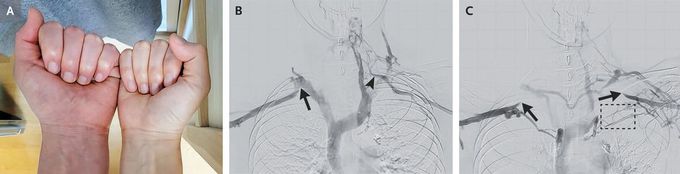

A 36-year-old woman was referred to the thoracic surgery clinic after she had presented with a 3-week history of swelling and bluish discoloration of the left arm and hand that occurred when she raised her arms (Panel A). The symptoms started after she had spent 10 days typing at a desk. Computed tomography of the chest identified no thromboses, and venography was subsequently performed. When the patient’s arms were down at her sides, blood flowed through a normal subclavian vein on the right side (Panel B, arrow). On the left side, blood flowed through an anatomical variant of the subclavian vein that connected to the jugular veins (Panel B, arrowhead). When the patient’s arms were elevated, blood flow through the subclavian veins on both sides was limited by compression between the first rib and the clavicle (Panel C, arrows); blood drainage from the left side was slower owing to smaller collateral vessels (box), which accounted for the patient’s symptoms on the left side. A diagnosis of venous thoracic outlet syndrome was made. Venous thoracic outlet syndrome occurs when the subclavian vein has thrombosis or is compressed in the costoclavicular space. In this case, the patient’s excessive desk work was thought to have caused tightening of the neck muscles that restricted a previously narrow costoclavicular space. A physical therapy program was prescribed. At the 3-month follow-up, her symptoms had abated.